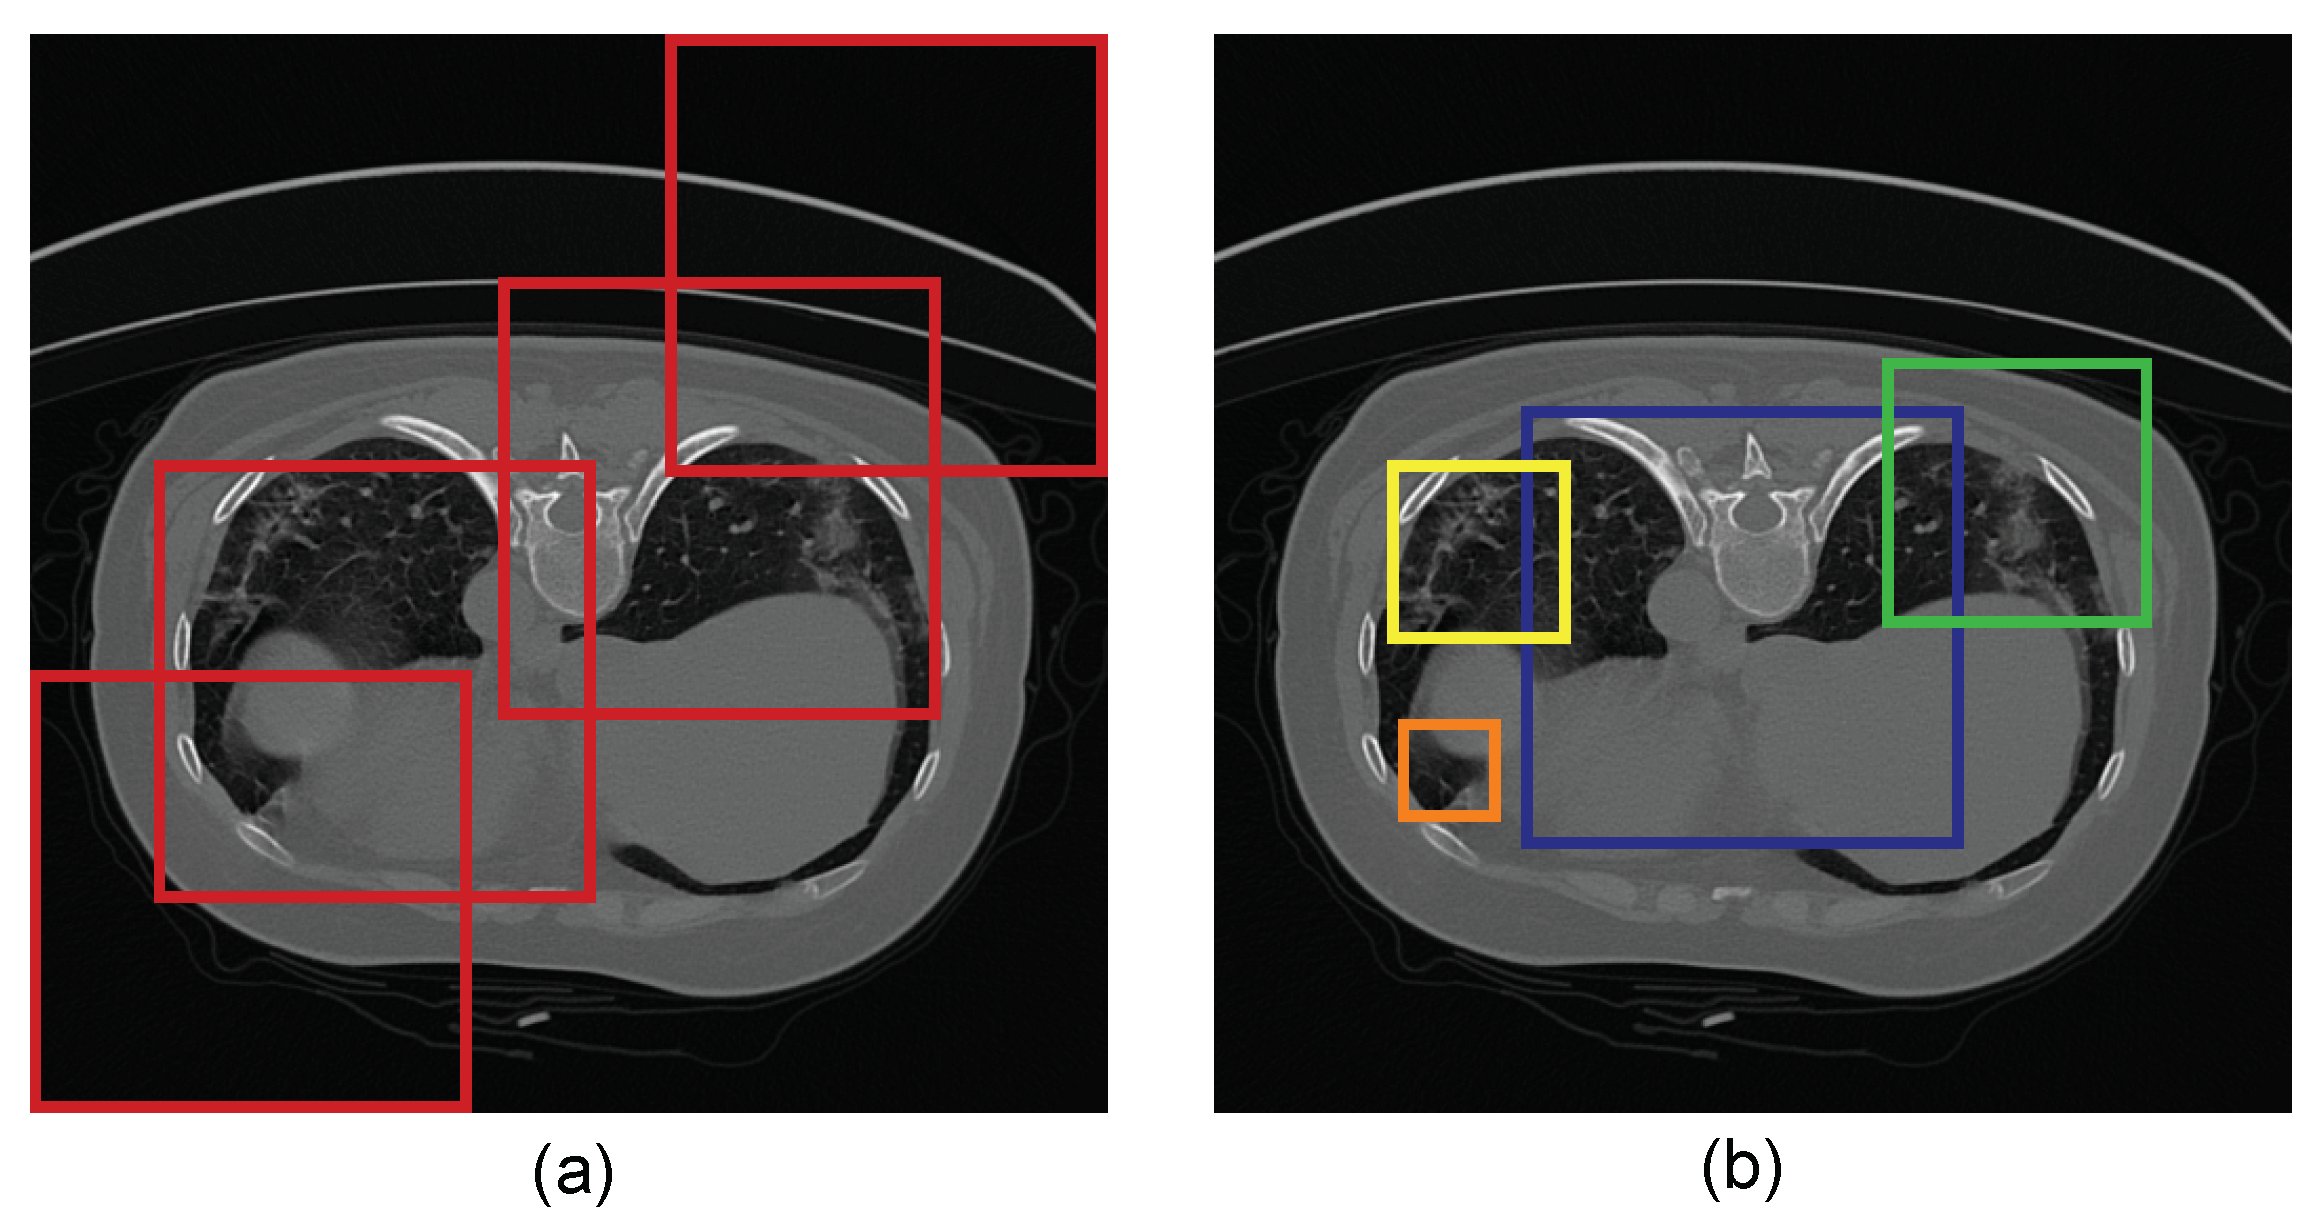

3.1.1. COVID-19 Lung CT Dataset